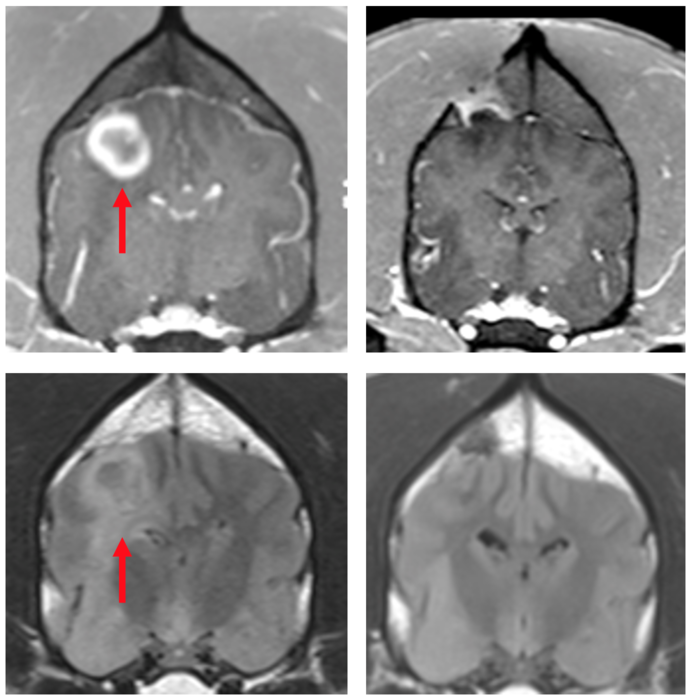

Peer-Reviewed PublicationIMAGE: MRI SCANS OF A DOG'S BRAIN WITH GLIOBLASTOMA. THE IMAGE IN THE TOP LEFT PANEL SHOWS A LARGE, BULKY TUMOR BEFORE BEING INJECTED WITH THE STING AGONIST. THE BOTTOM LEFT IMAGE SHOWS THE DIFFUSE INFILTRATION OF THE TUMOR BEFORE TREATMENT WITH THE STING AGONISTS. THE TOP RIGHT IMAGE SHOWS THE BRAIN 12 WEEKS LATER IN WHICH THE BULKY TUMOR HAS DISAPPEARED AFTER TREATMENT. THE BOTTOM RIGHT IMAGE SHOWS THE ASSOCIATED INFILTRATION HAS RESOLVED AFTER TREATMENT WITH THE STING AGONIST. view more

STING agonists can induce immunological responses that allow the immune system to fight otherwise immunologically resistant cancer cells. MRI scans taken of the canines over the course of the trial revealed that some of the dogs, even with a single dose, responded to the treatment with apparent reductions in their tumor volume, including one complete radiographic response, meaning the tumor completely disappeared. The findings lead the team to conclude this therapy can trigger a robust, innate anti-tumor immune response and may be highly effective on recalcitrant tumors such as glioblastoma in humans.